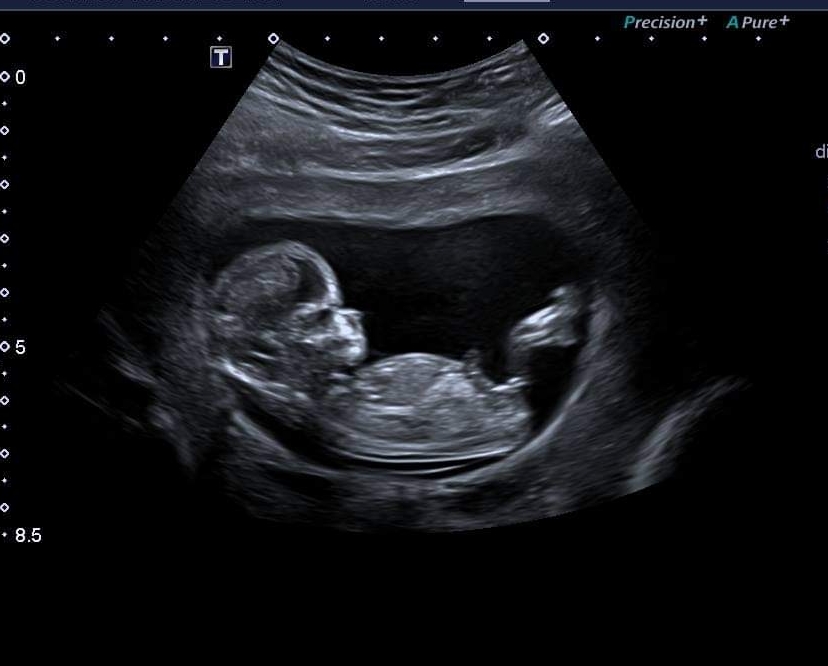

Would anyone be kind enough to guess the gender of my baby at 12+1? I'm not sure if there's a nub but I've included 3 pics so hopefully there's some clues.

Possibly a boy as there looks to be some stacking on picture 1. I’m not great at nun theory though. Picture 3 alone looks more girly as can’t see the stacking but I’m leaning blue

Thanks so much! Definitely not a clear one, even the skull looks girly in some pics and boy in others